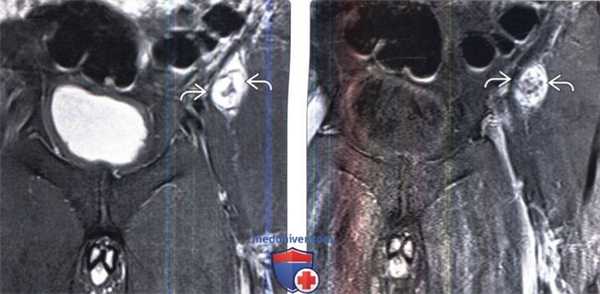

(Слева) Злокачественные опухоли оболочек периферических нервов (ЗООПН) нередко поражают крупные нервные стволы. Здесь, например, представлена опухоль седалищного нерва, представляющая собой веретеновидной формы дольчатое интраневральное образование. Эти опухоли могут распространяться вдоль оболочек нерва и образовывать сателлитные узелки.

(Справа) На фронтальном FS Т1-ВИ с КУ представлено массивное неравномерно накапливающее контраст объемное образование правой половины таза, распространяющееся через крестцовое отверстие в спинномозговой канал и через седалищную вырезку в ягодичную область. (Слева) Аксиальный срез, Т1-ВИ с КУ: гантелеобразной формы опухоль шейного отдела позвоночника. Видны признаки инфильтрации опухолью паравертебральных мягких тканей и инвазии опухоли в паренхиму спинного мозга.

(Справа) Аксиальный срез, Т1-ВИ с КУ, пациент с НФ1: нейрофибромы (НФ) в просвете левого неврального отверстия и спинномозгового канала. Накапливающая контраст опухоль в толще правой крестцово-остистой мышцы отличается несколько нечеткими границами и является гистологически верифицированной ЗООПН.